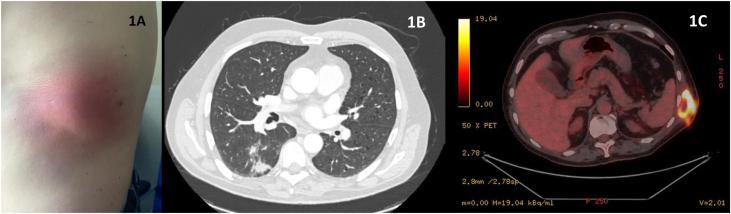

https://cdn.ncbi.nlm.nih.gov/pmc/blobs/9515/11869947/480dbe37bcda/gr1.jpg